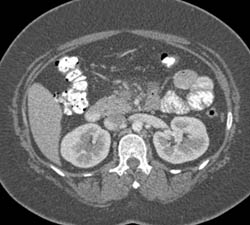

Acute Pancreatitis With Pancreatic Necrosis